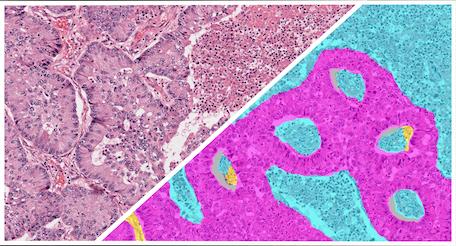

The Gastric H&E Tumor Tissue Detection App is a pre-trained HALO AI masking classifier designed to segment tumor, stroma, necrosis/other, and glass areas across H&E-stained whole slide images of gastric cancer.

The Ovarian H&E Tumor Tissue Detection App is a pre-trained HALO AI masking classifier designed to segment tumor, stroma, necrosis/other, and glass area across H&E-stained whole slide images of ovarian cancer.

High levels of variability are often encountered in image analysis but is no match for HALO AI. Common sources of variability include diverse morphologies, alterations of morphologies from staining protocols, differences in tissue quality, uneven staining, and more.

HALO AI can be easily trained to accommodate variability to deliver accurate segmentation and classification results across large studies. HALO AI can even be trained to work across vastly different stains such as PAMS, Trichrome, H&E, and IHC.